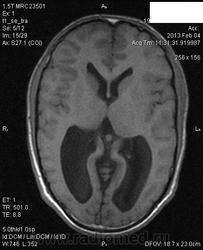

Объемное образование четверохолмной пластинки? Водопровод мозга компремирован. Образование изоинтенсивное во всех типах взвешенности, не накапливает контрастный препарат. Внутренняя окклюзионная тривентрикулярная гидроцефалия.Уважаемые коллеги, может ли иметь место аномалия развития четверохолмной пластинки (в литературе не встречалась, а вдруг бывает)?

Какая-нибудь гамартома, по анологии с гамартомой серого бугра.

А где гидроцефалия-то? Треттий не расширен, передние рога тоже. Есть только колпоцефалия. Гипогенезия мозолистого тела.

Может быть еще астроцитома низкой степени злокачественности. Они тоже не копят контраст. Гидроцефалии по-прежнему не вижу. Не может при гидроцефалии расширяться только задний отдел третьего желудочка и задние рога. В "задних отделах третьего" вероятно небольшая киста промежуточного паруса.

Спасибо Вам большое! Пока не получается добавить снимки в коронале и аксиале сканами выше, там будет видно, что передние рога также асимметрично расширены (D до 24см; S до 2,2см). На Кт от 2011г. и 2012г  писали, что четверохолмная пластинка увеличена, без динамики в сравнении с предыдущим исследованием. Внутреннюю гидроцефалию ставили в 2007г, 2011, 2012г. Оперирован по поводу аномалии Арнольда -Киари-декомпрессивная трепанация ЗЧЯ (не вижу этой аномалии).